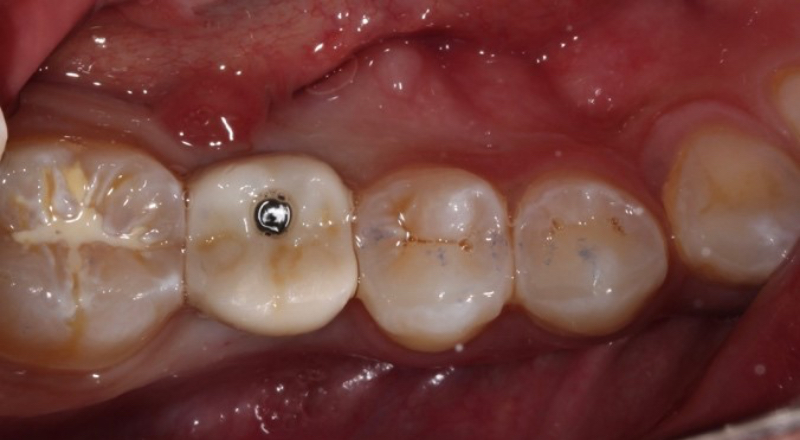

Two main advantages of screw-retained implant crowns are that they minimize the risk of peri-implantitis compared to cement-retained implant crowns and are also easier to retrieve. The ability to retrieve the restoration is helpful if the implant crown needs to be repaired or replaced due to fractured porcelain or an open contact between the implant crown and the natural tooth5.

However, drawbacks of a screw-retained design are that these restorations can be challenging to seat on the implant platform, and the presence of a screw access hole can lead to an unesthetic result if not appropriately managed.

The abutment-crown complex now acts like a screw-retained restoration ready to be delivered.